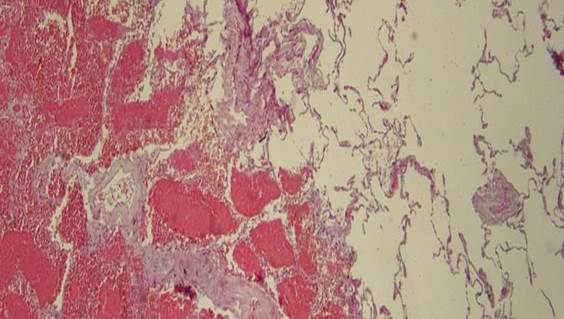

При проведении аутопсии животных из ЭГ были выявлены следующие характерные признаки: острая эмфизема легких, петехиальные кровоизлияния под плеврой (рис. 1-3).

Рис. 2. Эмфизема легкого. Окраска гематоксилином и эозином, х100

Источник: составлено авторами на основе [7].

Рис. 3. Субплевральное кровоизлияние, эмфизема легкого.

Окраска гематоксилином и эозином, х100

Наряду с этим отмечалась воздушная эмболия сосудов легких, лимфогемия грудного лимфатического протока (рис. 4, 5).

Рис. 4. Воздушная эмболия: пузырьки воздуха в вене легкого.

Окраска гематоксилином и эозином, х400